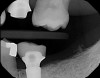

Fig 7. Preoperative radiograph showing previous endodontic therapy on tooth No. 8.

Figure 7

Fig 11. Radiograph of healed implant site No. 8 at 3 months.

Figure 11

Plugging into digital workflows provides opportunities to integrate CAD/CAM technologies at every step of the treatment process for dental implants. In another example, a patient presented with a failing tooth No. 8 (Figure 6 and Figure 7). After discussing treatment options, the patient chose to forgo any treatment to address tooth and soft-tissue asymmetries and wanted to proceed with a dental implant-supported restoration without additional treatment. After integrated 3-dimensional planning, the tooth was extracted, and then an implant and the final custom CAD/CAM abutment (titanium base with zirconia supra-structure) were placed with a provisional restoration in the same visit (Figure 8 and Figure 9). Soft-tissue grafting was also done at the same visit to address the deficient buccal tissue height on No. 8 (Figure 10). At 3 months, the patient presented for the final restoration, with excellent healing around the implant (Figure 11) and soft-tissue healing guided by the custom abutment (Figure 12).